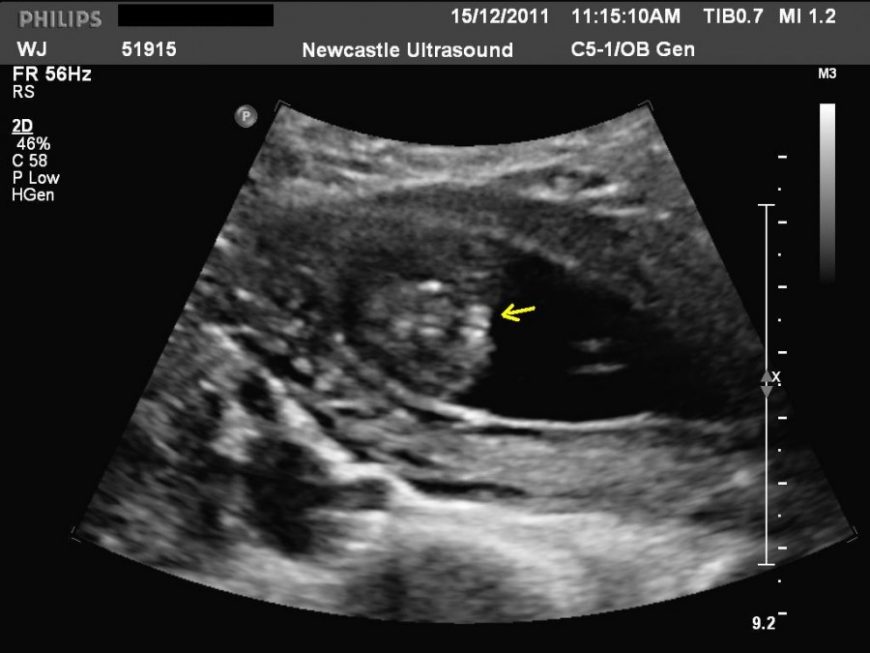

9 Недель Размер Плода Фото⚡ 👉🏻👉🏻👉🏻 ВСЯ ИНФОРМАЦИЯ ДОСТУПНА ЗДЕСЬ, КЛИКАЙ 👈🏻👈🏻👈🏻9 Недель Размер Плода Фото